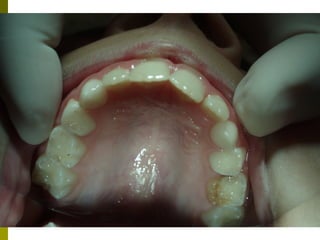

   Οι μασητικές επιφάνειες των οπισθίων δοντιών

ευνοούν την κατακράτηση τροφών και μικροβίων και

συχνά τερηδονίζονται αμέσως μετά την ανατολή τους.

   Έρευνα της Ελληνικής Οδοντιατρικής Ομοσπονδίας

έδειξε ότι σε παιδιά ηλικίας 12 ετών το 83% των

τερηδονισμένων επιφανειών παρατηρείται στις

μασητικές επιφάνειες      (Ουλής Κ.Ι. συν. Ελληνικά

Στοματολογικά Χρονικά 2009’ 53(3)΄97-120)

   Επίσης και μετά από παρακολούθηση έως 10 - 15 έτη, μόνο

το 30 -40% των δοντιών με κάλυψη είχαν μασητικές

αποκαταστάσεις, σε σχέση με 60 -80% των δοντιών χωρίς

καλύψεις.

   Μελέτες έχουν δείξει μείωση της τερηδόνας ,μετά την

τοποθέτηση ΚΟΣ, 85 -37 % μετά από 2 – 6 έτη

    οι προληπτικές καλύψεις θα πρέπει να εφαρμόζονται

ανάλογα με τον βαθμό κινδύνου ανάπτυξης τερηδόνας των

ατόμων, ή των επιφανειών επιλεκτικά και εξατομηκευμένα